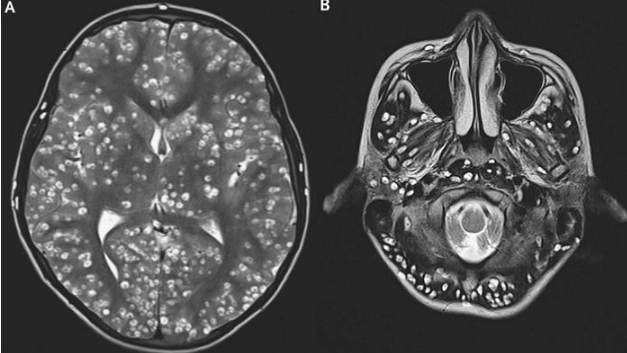

診断による結果、両親さえもが衝撃的な診断を受けました。MRI撮影結果を見てみたところ、少年の脳に多くの穴が写っていることが確認されたというのです。

その穴の正体は、嚢胞性病変というものであり、医療スタッフ陣はこのような症状が「神経状嚢虫症」の一環だと説明しました。

神経状嚢虫症は、よく焼けていない豚肉を食べたときに生じるといい、肉の中の寄生虫によって脳が損傷される病気だそうです。症状には、嘔吐や頭痛、発作の症状が現れるといいます。